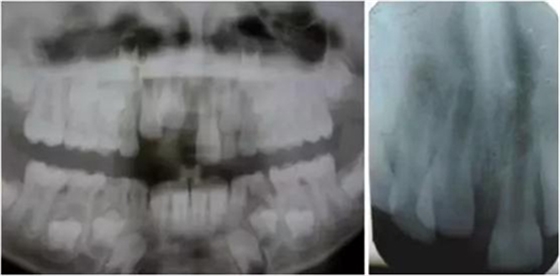

影像學(xué)檢查:根尖片以及全景片(圖2)提示牙槽骨骨折,根尖挫入至唇側(cè)骨板或鼻底。根尖片提示牙11,12 和21根尖發(fā)育不完全,呈喇叭口狀。受累牙的根管壁薄且不完全成形(圖2)。牙片顯示沒有冠折和根折。

( 圖2)